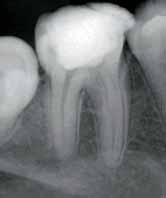

hypochlorite and hydrogen peroxide and then washed with saline. A closed dressing with calcium hydroxide was given and patient recalled after one month. Thereafter, periodic monthly appointments were given where the canal was irrigatedand closed irrigation with calcium hydroxide was given. After around 14 months after the first visit the swelling was completely absent and patient reported no pain. The periapical radioluscency was still present though localized to the periapical and reduced to around 5mm in diameter (Fig2a & b). This time the canals were obturated using lateral condensation technique (Fig 3). And the patient recalled after six months for a review. Six months after obturation it was seen that the periapical radioluscencywas almost absent with a mild crescent shaped radioluscent around the apex (Fig 4a & b). The patient had no symptoms to report. During the intervening six months the patient had crowns made to correct the discoloration. The patient was recalled after a period of six months to further review the healing.

Fig 3: Obturation (IOPA) Fig 5: Post Obturation 1 year (IOPA) Fig 4a: Post Obturation 6 months (IOPA) Fig 4b: Post Obturation 6 months (IOPA)